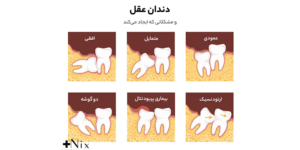

دندان عقل یا مولر سوم آخرین دندانی است که معمولاً بین ۱۷ تا ۲۵ سالگی در دهان رشد میکند. از آنجا که رشد این دندان دیرتر از بقیه دندانها آغاز میشود، در بسیاری از افراد فک فضای کافی برای رشد کامل آن ندارد.

به همین دلیل، رشد دندان عقل معمولاً ناقص است و دندان بهصورت نیمهنهفته یا کاملاً نهفته در لثه میماند.

وقتی فضای فک محدود باشد، دندان عقل به دندانهای مجاور فشار وارد میکند. این فشار درد شدیدی ایجاد میکند و گاهی باعث جابهجایی دندانهای دیگر میشود. در چنین شرایطی، لثه اطراف دندان ملتهب میشود و احتمال عفونت افزایش مییابد. باقیماندن ذرات غذا و باکتریها در این ناحیه باعث ایجاد التهاب، کیست یا آبسه میشود. در برخی موارد، رشد ناصحیح دندان ممکن است به استخوان فک و دندانهای کناری آسیب برساند.